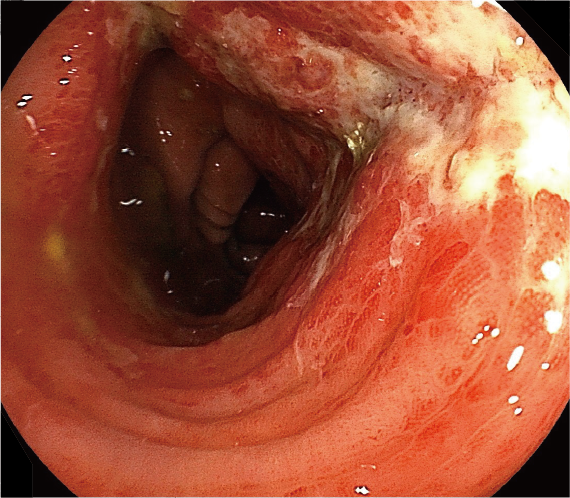

10日前から下痢、血便を認める患者さんの診断名は?

- 出血源の検索を目的に、大腸内視鏡検査および生検組織学的検査を施行した。

●大腸内視鏡検査